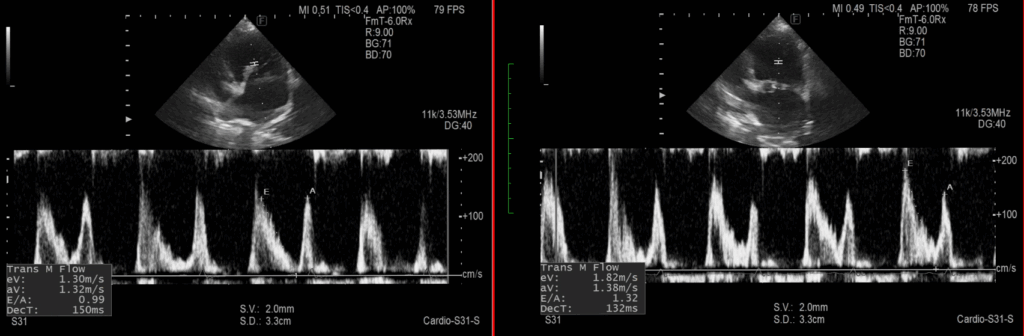

エコー画像は←が治療後で→が治療前です。

・E波の減高

左室流入波形の早期波であるE波が下がっています。

左心室から大動脈に血流が流れやすくなって左心房圧が下がり、循環動態が改善傾向であることを示唆します。